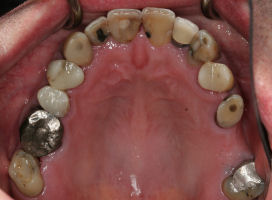

Before/After